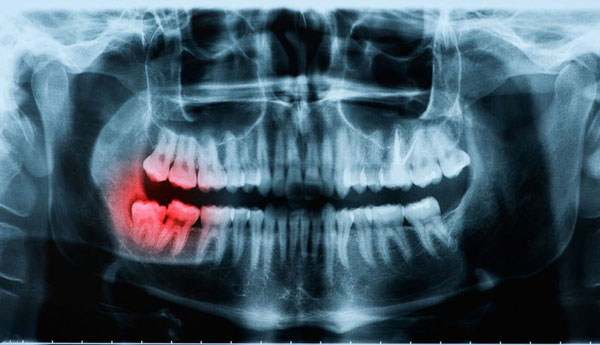

Hãy tìm hiểu thật kỹ và chọn những nha khoa uy tín, được cấp phép hoạt động, có trang bị đầy đủ máy móc hiện đại, bác sĩ giỏi, tay nghề cao. Qua thăm khám trực tiếp và phim chụp X-quang bác sĩ sẽ xác định chính xác tình trạng răng miệng, mức độ sai lệch, để có thể chỉ định có nên nhổ răng khôn không. Đồng thời thực hiện đúng kỹ thuật, giúp xử lý răng khôn nhanh chóng, an toàn và phát hiện sớm những bất thường nếu có.